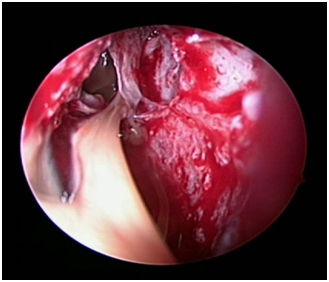

The patient was posted for endoscopic marsupialization of the mucoceles. The mucocele sac from ethmoid sinus was incised and the mucus was drained out (Figure 4 & 5) following which another mucocele sac was identified in the frontal sinus and was drained out (Figure 6 & 7) thus confirming the diagnosis of multiple mucocele introperately.

Figure 4 Intraoperative picture showing right ethmoidal mucocele.

Figure 5 Intraoperative picture taken after draining right ethmoidal mucocele.